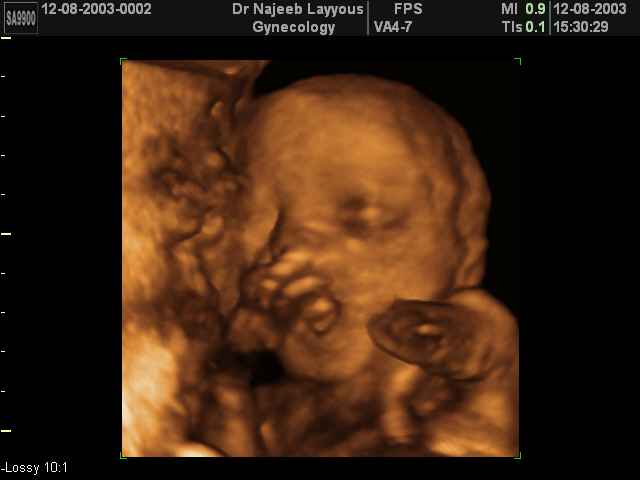

- Fetal Behavior Ultrasound Photos

Ultrasound Photos in 3D showing Fetal Behavior Inside the uterus | Dr N Layyous